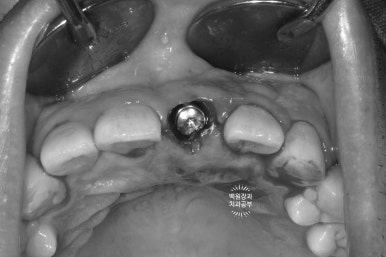

뒷 부분을 하늘색 임시재료로 메꿔드렸고,

환자분은 왼쪽 상태로 귀가하실 수 있었습니다.

위처럼 뿌리만 있었던 치아를 제거하고,

발치 즉시 임플란트를 시행 후 뼈이식과 임시치아 연결을 통해

아래처럼 귀가하실 수 있게 되었던 것입니다.

모두가 다 하루에 가능한 임플란트 수술과정이었습니다.

비록 임시치아는 레진 치아라 다소 어색함이 있을 수 있으나,

환자분께서 매우 만족해하셨습니다.